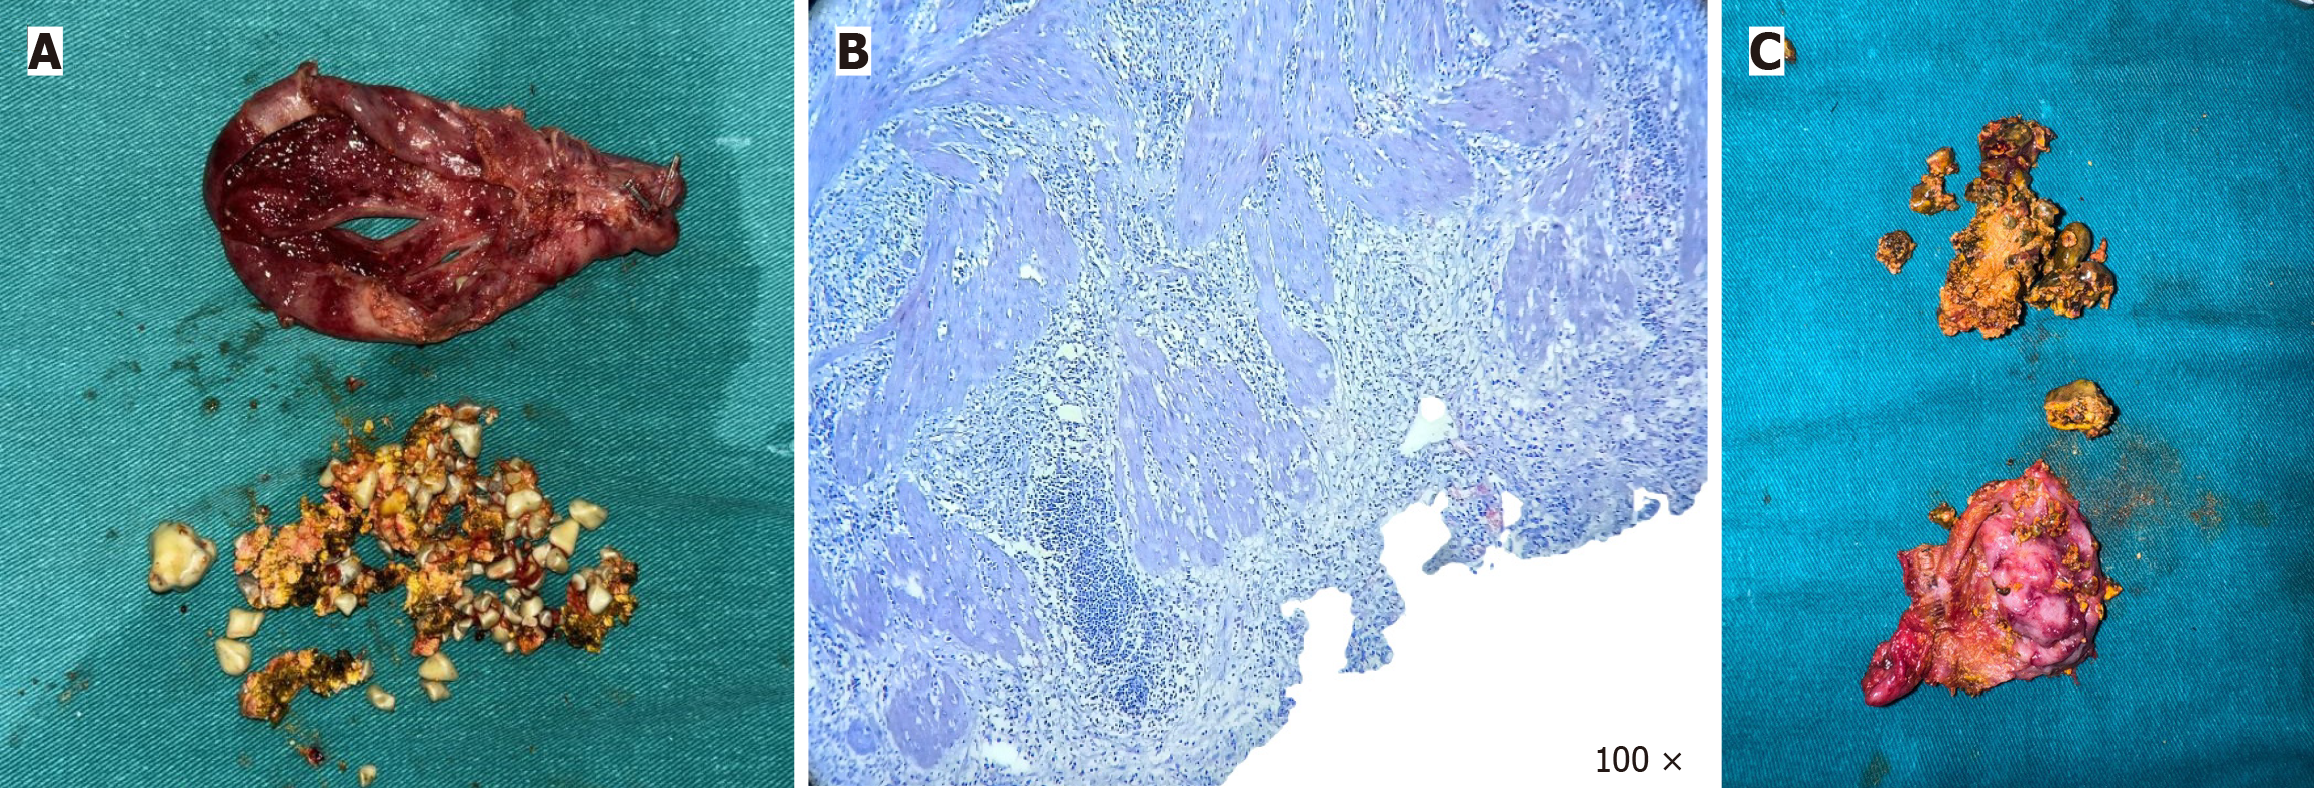

Symptomatic cholelithiasis in SIT (case 1) and cholelithiasis with choledocholithiasis in SIT (case 2) (Figure 4).

Both patients underwent elective laparoscopic cholecystectomy using a mirror-image four-port configuration (Figure 5). In both cases, the critical view of safety was achieved prior to division of the cystic duct and artery. Intraoperative findings confirmed left-sided gallbladder anatomy (Figure 6A). Dissection was carried out with careful orientation to Rouvier’s sulcus, and the critical view of safety was achieved before division of the cystic duct and artery (Figure 6B and C). The gallbladder was retrieved through the epigastric port (Figure 6D).

Both patients had an uneventful postoperative course and were discharged on postoperative day one. Clinical follow-up at 30 days and 6 months revealed no complications or recurrent biliary symptoms.